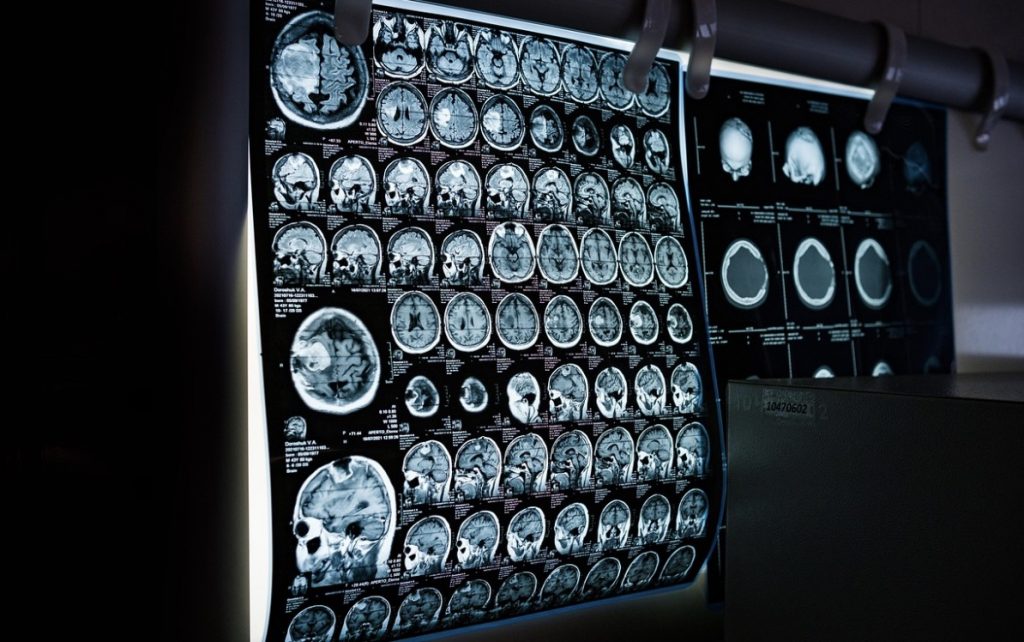

Brain injuries can vary dramatically in type and severity. They include traumatic brain injuries (TBIs) resulting from external forces, such as falls or accidents, and non-traumatic injuries from internal factors like strokes or tumors. Each type presents unique challenges and can have differing effects on a person’s physical and cognitive capabilities.